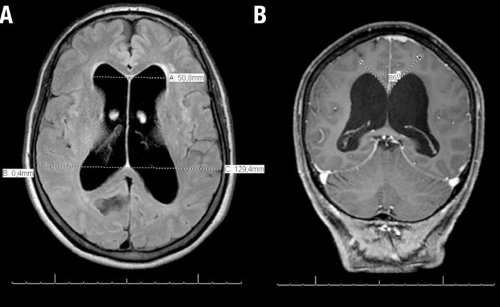

図1 特発性正常圧水頭症患者の頭部MRI画像

脳室の拡大が目立つ(A)が、高位円蓋部、正中部(頭頂部)は脳溝が狭小化(B)している